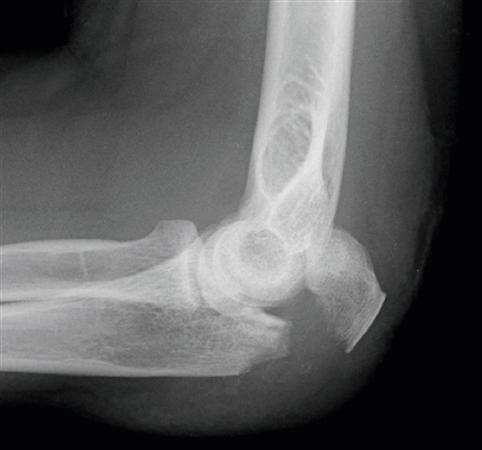

210

Outline clinical features of Olecranon Fractures, including age group and nerve affected.

Usually adults Check ulnar nerve status Check displacement on XR with elbow at 90deg - If displacement >2mm, need surgery - Can have radial head dislocation as well (A) Olecranon fracture with displacement (B) Fracture accompanied by radial head dislocation